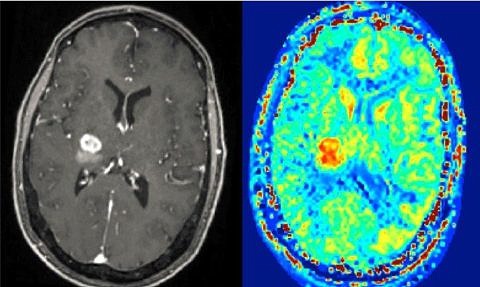

Mit Hilfe der Magnetresonanztomografie (MRT) lassen sich in der heutigen Medizin vor allem die Weichteile im menschlichen Körper sehr gut darstellen – und helfen in der Diagnostik, Veränderungen wie Tumoren zu erkennen. Viele Erkrankungen lösen allerdings bereits Veränderungen im Zellstoffwechsel aus, bevor im MRT tatsächlich eine substanzielle Strukturveränderung des Gewebes zu erkennen ist. Ein Forschungsteam der Friedrich-Alexander-Universität Erlangen-Nürnberg (FAU) um Prof. Dr. Moritz Zaiß, Professur für Multimodale Bildgebung in der klinischen Forschung, und der Technischen Universität Graz arbeitet jetzt an einem Verfahren, um bereits diese Stoffwechseländerungen im MRT sichtbar zu machen und so einen wichtigen Beitrag für die Früherkennung von Krankheiten durch MR-Biomarker zu leisten. Das Projekt wird von der Deutschen Forschungsgemeinschaft und dem österreichischen Fonds zur Förderung wissenschaftlicher Forschung mit 650.000 Euro gefördert.

Für die Diagnostik, gerade für die Früherkennung bestimmter Erkrankungen, wäre es allerdings wichtig, Gewebeveränderungen bereits in einem Stadium zu identifizieren, wenn sich lediglich im Zellstoffwechsel Unregelmäßigkeiten finden – typische frühe Anzeichen, dass etwas mit der Zelle nicht stimmt. Könnte man diesen Zellstoffwechsel ebenfalls in 3D sichtbar machen und auf diese Weise feststellen, wie hoch zum Beispiel der Kreatin-Gehalt oder der pH-Wert an bestimmten Stellen im Gewebe ist, wäre dies ein immenser Gewinn für die Medizin. Denn solche Werte sind häufig so genannte Biomarker, also messbare Hinweise im Körper auf bestimmte Erkrankungen.

Grundsätzlich könnte die Magnetresonanztomografie dies leisten, gerade die neuen leistungsstarken Hochfeld-Magnetresonanztomografen mit Feldstärken von sieben Tesla oder mehr. In verschiedenen Molekülen nämlich, die in der zellulären Struktur oder im Zellstoffwechsel vorkommen – etwa Proteine und Stoffwechselzwischenprodukte, so genannte Metaboliten – sind ebenfalls Wasserstoffatome enthalten sind, allerdings in deutlich geringerer Konzentration als in Wasser selbst. Ein Lösungsansatz ist das so genannte CEST-MRT: Die Abkürzung CEST steht für den „chemical exchange saturation transfer“, ein Verfahren, das sich den chemischen Prozess des Protonenaustauschs zu Nutze macht, um die Sensitivität des MRT so zu erhöhen, dass es auch auf die geringen Konzentrationen von Wasserstoffprotonen in Proteinen und Metaboliten anspringt. Das interessante an der CEST-MRT-Methode ist, dass sie nicht-invasiv ist und keine Kontrastmittel benötigt.